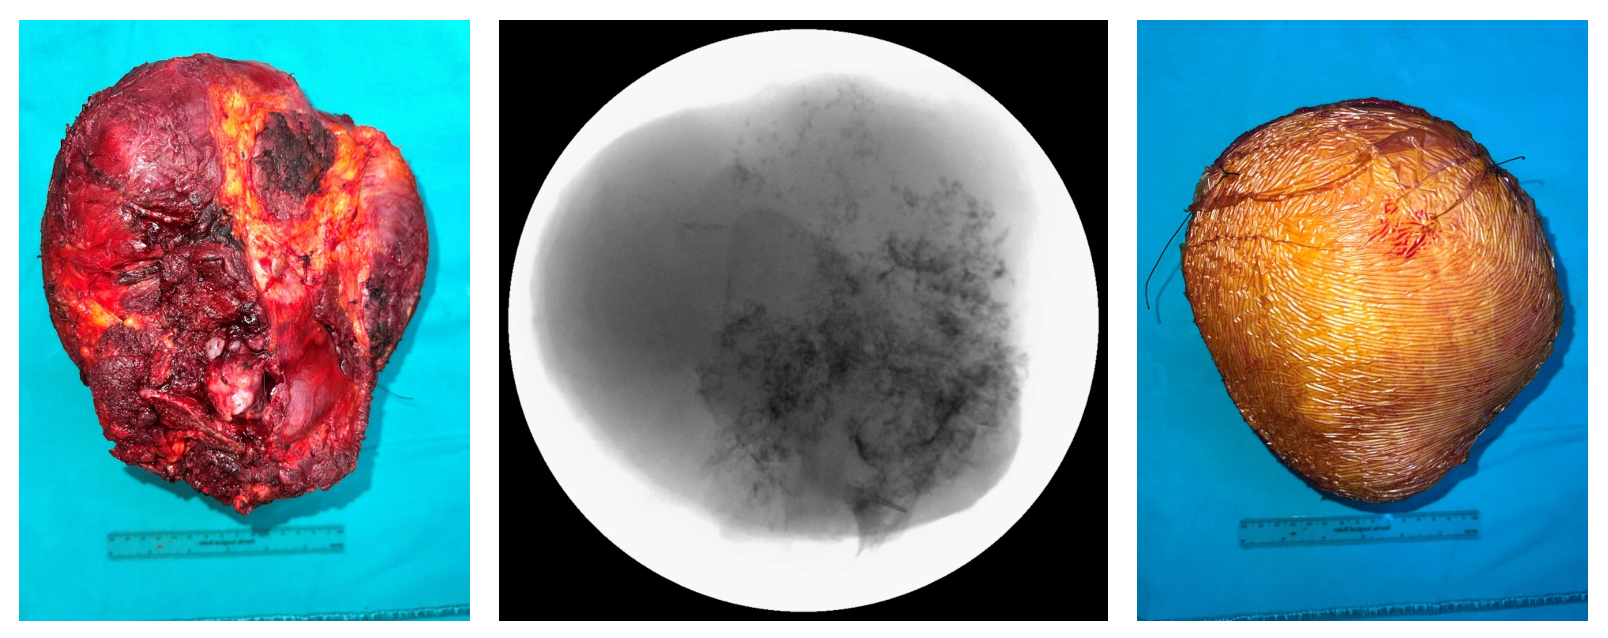

Ameliyat Esnası: Kitlenin klinik görüntüsü.

Ameliyat Esnası: Çıkarılan tümör dokusunun klinik ve skopi görüntüsü.